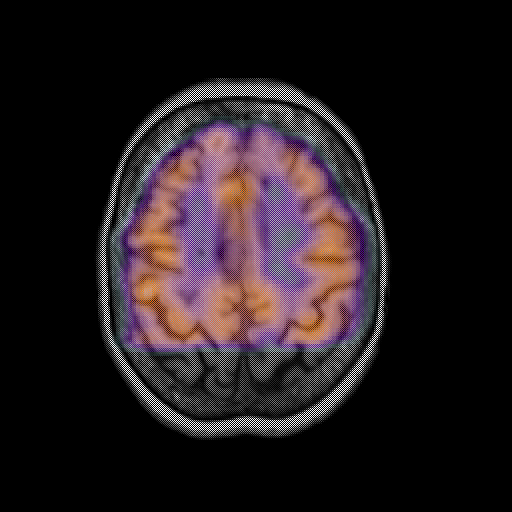

overlay: Slice 39

Slice 39

MRCBFCBF with

T1PDT2T1PDT2